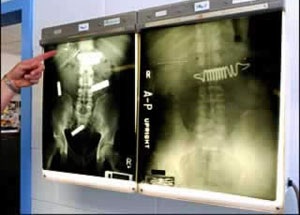

Còn tại nhà tù trung tâm thành phố Raleigh (Bắc Carolina, Mỹ), những tù nhân đã nuốt nhiều vật dụng để được ra chăm sóc ở các bệnh viện.

Kim băng

Hai viên pin

Chìa khóa ô tô